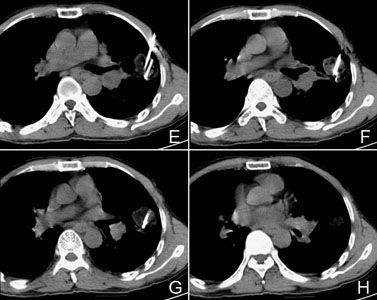

肿瘤微创靶向治疗技术-美国氩氦超冷刀,是世界上同时兼具零下150度超低温冷冻、介入热疗、200度大温差逆转和免疫增强等多重效能的高新科技医疗系统。优于单纯高热或单纯冷冻治疗。杀灭癌细胞更有效。 该技术属纯物理治疗,具有摧毁肿瘤治疗效果确切、治疗不导致癌细胞扩散、不损伤正常组织、与放化疗不同氩氦超冷刀治疗无毒副作用,还可以有效地调控细胞因子和抗体的分泌,。它是继射频消融治疗,微波,激光,超声聚集刀,伽玛刀等之后发展起来的肿瘤治疗高新技术。在治疗肺癌、肝癌、乳腺癌、肾肿瘤等实体肿瘤方面具有优势。

适应症:

肺癌治疗、肺部良性肿瘤、肝癌治疗、肝血管瘤、胰腺癌、乳腺癌、乳腺增生、脑瘤、脊髓膜瘤、前列腺癌、前列腺增生、肾癌、肾上腺肿瘤、会阴部肿瘤、子宫癌、宫颈癌、卵巢癌、阴茎癌、皮肤癌、黑色素瘤、血管瘤、骨肉瘤、扁桃体癌、咽喉部肿瘤、鼻咽癌、神经纤维瘤、脂肪肉瘤、口腔癌、舌癌、颌面部肿瘤、颈部肿瘤等。

尤其适用于早期、中期和晚期各期实体肿瘤的治疗,尤其是那些不能手术切除的中晚期患者、或因年龄大身体虚弱等各种原因不愿手术肿瘤的患者;是不愿承受放化疗副作用或放化疗及介入治疗等治疗效果不好肿瘤患者可以选择。